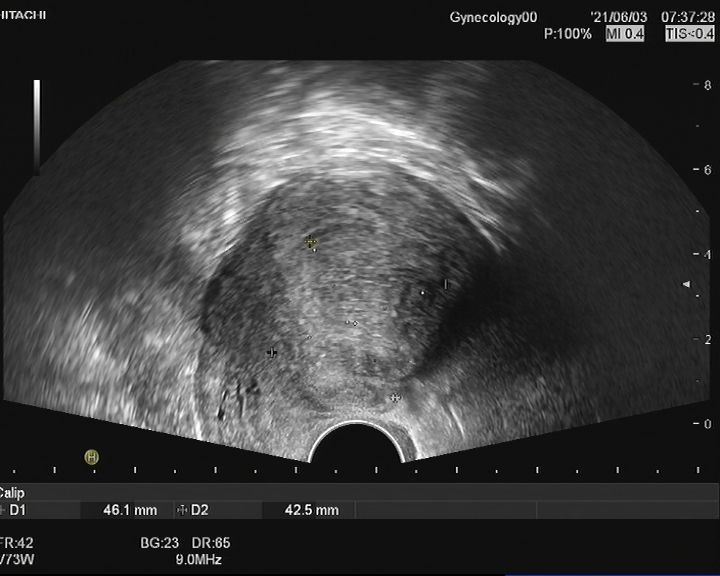

患者女,28岁,2021-06-07于青岛市妇女儿童医院就诊。 主诉:进行性痛经加重3年余。 现病史:患者月经初潮即有经期下腹痛,无需口服止痛药物。3年前痛经渐进性加重,目前经期腹痛VAS评分8分,伴恶心呕吐、肛周坠胀感。伴有非经期腹痛,VAS评分4分,持续4-5天,有深部性交痛。月经周期、经期及经量较前无明显改变。我院就诊超声提示:子宫后壁探及低回声结节,大小46mm*56mm*42mm,考虑子宫肌瘤。患者有明确生育要求,为求进一步治疗,门诊以“子宫腺肌病?子宫肌瘤?”收入院。患者自发病以来,神志清,精神可,饮食正常,经期夜间睡眠欠佳,体重较前无明显增减。 既往史:体健,否认慢性病及传染性疾病病史,否认外伤史,否认输血史,否认食物、药物过敏史。 月经及婚育史:既往月经规律,周期28-30天,经期5-6天,末次月经:2021-05-24。G1P0A1,2021年4月孕11周“稽留流产”行药物流产1次。 家族史:无特殊。 体格检查:T36.2℃,P77次/分,R18次/分,BP101/67mmHg,身高160cm,体重56kg。疼痛评分:0分。心、肺、腹部查体无异常。 专科查体: 妇科查体:外阴发育正常,阴道畅,宫颈光滑,子宫后位,增大如孕2月,固定、活动差,无压痛,双侧附件区未及异常。三合诊:左侧骶韧带触及触痛结节。 辅助检查: 2021-06-03 B超:子宫后位,宫体大小正常,形态规则,肌层内回声欠均匀,后壁肌层探及低回声结节,大小约46mm*56mm*42mm,边界清。宫腔内膜受压前移,厚10.1mm。宫颈形态正常。左侧卵巢探及液性暗区,大小约39mm*29mm,透声好,右侧卵巢大小正常。右侧附件区未见明显异常。 2021-06-07 肿瘤指标:糖类抗原CA19-9 52.21U/ml;糖类抗原CA125 112.9U/ml ↑; 2021-06-07 MRI提示:子宫后壁子宫腺肌病、盆腔子宫内膜异位症? 初步诊断: 2.盆腔子宫内膜异位症 3.不良孕产史 1.2021-06-08在镇静镇痛下行聚焦超声消融手术(FUAS)治疗。术后增强核磁检查提示子宫后壁腺肌病灶内无灌注区,子宫内膜及浆膜血流灌注正常。 2.2021-06-22术后第一次月经来潮,痛经较前减轻,VAS评分2-3分。术后辅助GnRh-a治疗3周期辅助治疗,同时口服钙片补钙治疗,用药期间闭经,无腹痛等不适。 3.GnRh-a治疗3周期后,2021-09-08复查B超:子宫后位,宫体大小正常,形态规则,肌层内回声欠均匀,后壁肌层探及高回声团,大小约38mm*37mm*26mm,边界清,内见少许血流信号。宫腔内膜受压前移,厚4.1mm。宫颈形态正常。双侧卵巢大小正常。双侧附件区未见明显异常。 4.2021-11-22月经复潮,经量正常,痛经VAS 2分,月经第5天开始口服地屈孕酮20mg QD,每月经周期20天,建议试孕半年。 5.2022-04-27随访复查,LMP:2022-02-24,停经9周,B超:子宫后位,体积增大,形态饱满,被膜光滑,后壁肌层回声不均匀,内见低回声区,较大范围约35mm*26mm,宫腔内见大小约32mm*31mm*24mm妊娠囊,张力可,内见胎芽,纵径22.4mm,心管搏动规律,妊娠囊下方探及不规则液性暗区,范围约21mm*8mm。双侧附件区未见明显异常。继续口服地屈孕酮10mg q8h保胎治疗。孕期进展顺利,2022-11-25外院足月剖宫产1女婴,体重3300g,Apgar评分10分-10分。 子宫内膜异位症和子宫腺肌病是妇科常见疾病。除了引起疼痛和月经改变,越来越多的证据表明,这两种疾病对女性的生殖功能有重要影响。临床可表现为不孕不育和流产等,尤其是早期流产[1]。 本例患者B超提示“子宫肌瘤”可能,但后续评估更符合子宫腺肌病。弥漫性子宫腺肌病的超声检查准确性较高,但子宫腺肌瘤超声表现与子宫肌瘤相似,临床诊断需要结合患者的症状、CA125水平综合判断。相比超声,磁共振检查对子宫腺肌病的分型更有优势,也更容易发现合并的盆腔子宫内膜异位症。后位子宫的后壁腺肌病灶往往合并子宫直肠陷凹的内异病灶,本例患者即属于该情况,治疗策略应兼顾两种疾病并同时考虑患者的生育需求。 针对子宫腺肌病,传统的病灶切除手术对子宫损伤较大,合并盆腔子宫内膜异位症时,手术操作也较困难,所以对于有生育需求的患者选择手术治疗需要相当慎重。聚焦超声消融术(HIFU)可选择性消融子宫腺肌病病灶、使病灶缩小,同时保护子宫完整性,从而达到减轻症状、缩小病灶、改善生育的目的[2]。但无法同时消融盆腔子宫内膜异位病灶,需要联合药物综合治疗。 子宫腺肌病和子宫内膜异位症的慢病管理理念已逐渐被认可,药物治疗是基石。而目前一线用药促性腺激素释放激素激动剂、地诺孕素等均会抑制排卵,有生育需求的患者备孕时需要停药。而停药后的试孕期病灶复发和进展风险较高,从而影响妊娠几率。地屈孕酮10-20mg/d可缓解内异症痛经,不抑制排卵,兼顾子宫腺肌病和盆腔子宫内膜异位症患者的治疗和备孕。此外,对于疑有黄体功能不足者黄体期使用地屈孕酮还可能提高自然受孕率,备孕期周期性用药副作用低,安全性高。 子宫腺肌病不仅可导致患者的生育力低下,诸如排卵障碍、不孕、流产、早产、死产、胎儿生长受限等,还可导致妊娠期母亲并发症如剖宫产率增加、子痫前期、前置胎盘及胎盘早剥等[3],一旦妊娠应更加积极的给予保胎治疗和严密随访,积极补充孕酮以抑制子宫平滑肌收缩,尽可能提高活产率。 子宫腺肌病和子宫内膜异位症具有类似的发病机制,也常常合并存在,严重影响女性的生殖健康。针对两种疾病的治疗应规范化、个体化、微创化。给予规范用药或手术治疗,减灭和消除病灶,减轻临床症状的同时,应充分考虑患者的主要诉求、年龄和生育需求,尽可能选取创伤小的治疗方式。重视患者全生命周期的管理,早诊早治、促进生育、长期管理预防复发,避免反复手术带来的创伤,定期随访,警惕恶变。 该患者28岁,痛经伴非经期腹痛,临床诊断符合子宫腺肌瘤合并子宫内膜异位症。既往不良孕产史,有明确生育需求,具有治疗指征。针对后壁子宫腺肌瘤传统手术方式对子宫损伤较大不利于患者后续妊娠,康医生选择了聚焦超声消融术治疗缩小子宫腺肌病病灶,减轻患者痛经并改善子宫形态,有利于提高妊娠几率。 子宫腺肌病和子宫内膜异位症在年轻患者中复发几率极高,可谓“不死的癌症”,当患者又有生育需求时,如何兼顾治疗和生育确实给我们提出了较高的要求。该患者在停用GnRh-a后月经来潮,备孕期间给予口服地屈孕酮稳定病灶、改善痛经,同时不会影响下丘脑-垂体-卵巢轴(HPO轴)而抑制排卵,还能提高自然受孕几率,可谓一举两得。 患者服用地屈孕酮3个月后便顺利妊娠,体现了治疗的有效性。更难能可贵的是,康医生重视子宫腺肌病患者的孕期管理,妊娠后继续给予口服地屈孕酮积极保胎,抑制子宫平滑肌收缩,也体现了将子宫腺肌病患者作为高危孕产妇管理的治疗理念。 参考文献: